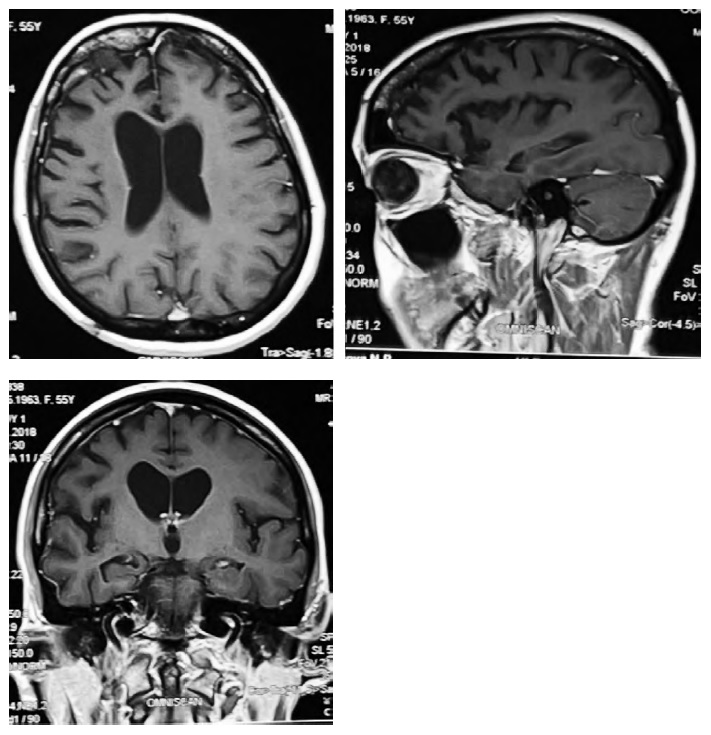

КБС-БКЯ. Женщина, 58 лет. В возрасте 57 лет появились легкие нарушения речи, аффективные расстройства, нарушения ночного сна. При осмотре через 10 мес после начала болезни в неврологическом статусе обращали на себя внимание лёгкий постуральный тремор рук (D > S), апраксия в руках (трудности при копировании жестов, D > S), когнитивные нарушения (MоCA — 18/30 баллов, Адденбрукская шкала ACE-R — 75/100 баллов). При осмотре через 11 мес после дебюта отмечено значительное нарастание когнитивных нарушений с выраженным нарушением понимания инструкций и появлением заторможенности мышления, нарастание выраженности апраксии в руках (D > S), появление мозжечковых нарушений (динамическая и статико-локомоторная атаксия). При осмотре через 12 мес после дебюта появились глазодвигательные нарушения (ограничение взора вниз), левитация правой руки, синдром чужой руки справа, дистония обеих рук и миоклонии (D > S), галлюцинации; усилилась выраженность когнитивных и речевых нарушений (мутизм).

На МРТ головного мозга (рис. 3) визуализируется повышение интенсивности сигнала в режиме ДВИ в сером веществе коры головного мозга в проекции центральных извилин, височных долей, а также в головках хвостатых ядер. Учитывая комбинацию корковых (апраксия, феномен чужой конечности) и подкорковых нарушений (дистония, миоклонии), согласно критериям M.J. Armstrong и соавт. [1], можно диагностировать у данной пациентки КБС. Однако, учитывая скорость прогрессирования заболевания, типичную клиническую картину (быстропрогрессирующая деменция, мозжечковый синдром, экстрапирамидные нарушения, акинетический мутизм, галлюцинации), а также типичные изменения на МРТ в режиме ДВИ и ЭЭГ (периодические трехфазные острые волны), пациентке был установлен диагноз вероятной спорадической БКЯ [15] (ДНК-диагностика на наличие мутации в гене PRNP дала отрицательный результат).

Рис. 3. МРТ головного мозга (режим ДВИ) пациентки с БКЯ при наличии КБС через 10 (А) и 12 мес (В) после дебюта заболевания. / Fig. 3. Brain MRI (DWI mode) of patient with CJD, presenting with CBS, 10 (A) and 12 (B) months after disease onset.